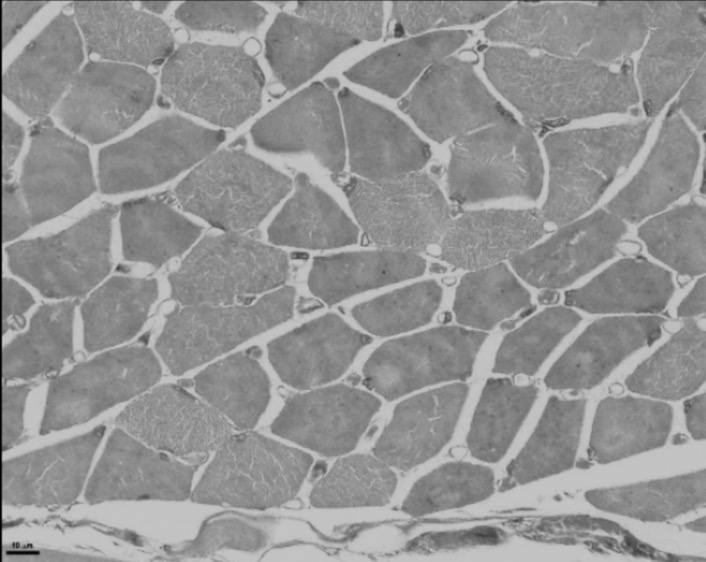

Deep-learning models have been successful in biomedical image segmentation. To generalize for real-world deployment, test-time augmentation (TTA) methods are often used to transform the test image into different versions that are hopefully closer to the training domain. Unfortunately, due to the vast diversity of instance scale and image styles, many augmented test images produce undesirable results, thus lowering the overall performance. This work proposes a new TTA framework, S$^3$-TTA, which selects the suitable image scale and style for each test image based on a transformation consistency metric. In addition, S$^3$-TTA constructs an end-to-end augmentation-segmentation joint-training pipeline to ensure a task-oriented augmentation. On public benchmarks for cell and lung segmentation, S$^3$-TTA demonstrates improvements over the prior art by 3.4% and 1.3%, respectively, by simply augmenting the input data in testing phase.